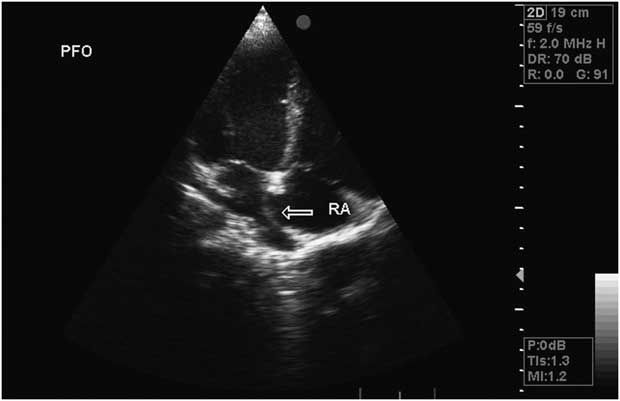

An atrial septal aneurysm (ASA) is a rare but well recognized and localized saccular deformity of the atrial septum that bulges into the right or left atrium with uncertain clinical significance. [1,2] Diagnosis can be established using transthoracic (TTE) and transesophageal echocardiography.

An atrial septal aneurysm (ASA) is a rare but well-recognized cardiac abnormality of uncertain clinical significance. ASA has been reported as an unexpected finding during autopsy1 but may also be diagnosed in living patients by echocardiographic techniques.

An atrial septal aneurysm (ASA) is a congenital malformation of the atrial septum characterized by bulging of the septum overlying the fossa ovalis region into either atrium. The prevalence of ASA varies according to the diagnostic method used and to the type of population studied.

Atrial septal aneurysm (ASA) is a congenital deformity of the interatrial septum with a prevalence of 1-2% in the adult population. Although ASA has been supposed to be an incidental finding in echocardiographic examination, its structural and clinical associations have gained an increasing interest.

What is PFO with atrial septal aneurysm?

The patent foramen ovale (PFO) is a slitlike interatrial opening that is present in about 27% of the general population. It is 1 of the major causes of a cardiac right‐to‐left shunt (RLS). An atrial septal aneurysm (ASA) is a congenital bulging of the atrial septum involving the fossa ovalis region.